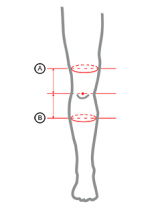

Orteza posiada dwa niezależne zespoły pasów wzmacniających wykonane z taśm VELCRO oraz anatomicznie wyprofilowany pierścień o właściwościach przeciwgrzybiczych doskonale stabilizujący rzepkę (staw rzepkowo-udowy). Wyrób wyposażono w jednoosiowe szyny boczne, wykonane z wysokiej jakości tworzywa sztucznego zbrojonego włóknami węglowymi. Zastąpienie tradycyjnych szyn metalowych szynami z dodatkiem włókien węglowych, pozwoliło na kilkakrotnie zmniejszenie wagi ortezy. Układ szyn w ortezie oraz ich specyficzna elastyczność, powoduje właściwe przyleganie wyrobu do zabezpieczonej kończyny i pozwala na uzyskanie doskonałej stabilizacji zabezpieczonego stawu. Szyny zostały wyposażone w specjalne zegary umożliwiające regulację kąta zgięcia i wyprostu co 15 stopni. Wewnętrzna perforacja ortezy zapewnia doskonałe odprowadzania wilgoci i nadmiaru ciepła ze skóry pacjenta.

Całkowita długość ortezy: 45 cm